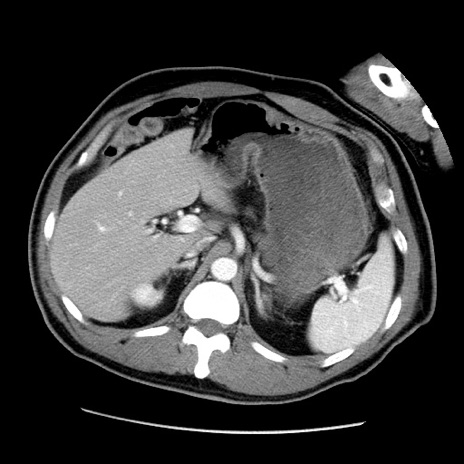

症例

冠状断像